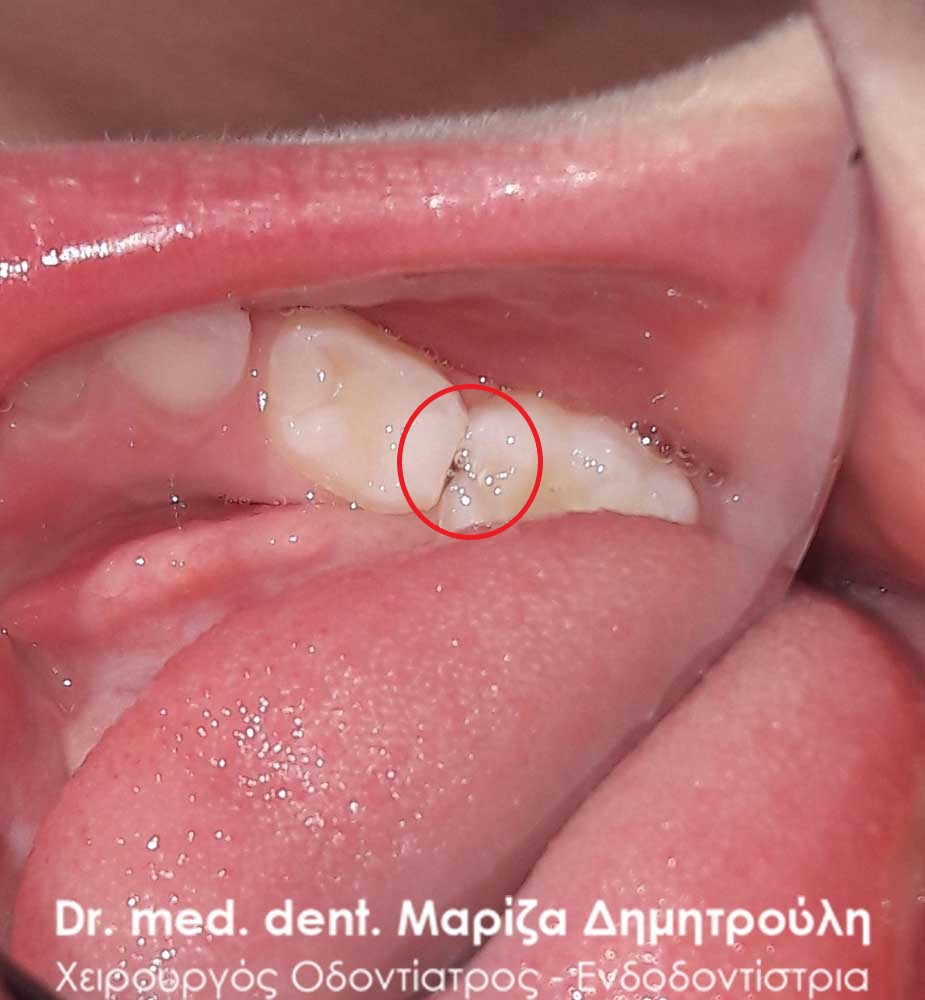

Περιστατικό – Σφραγίσματα παιδικών δοντιών

Κορίτσι ηλικίας 9 ετών αναφέρει οτι πονάει στην πάνω αριστερή πλευρά του στόματος της όταν μασάει. Μετά την κλινική εξέταση διαπιστώθηκε η ύπαρξη 2 τερηδονισμένων δοντιών. Στον πρώτο μόνιμο αριστερό γομφίο είναι εμφανής η ύπαρξη τερηδόνας, της οποίας η έκταση αποδείχτηκε αρκετά βαθιά κατά τη διάνοιξη του δοντιού. Στο δεύτερο νεογιλό (παιδικό) γομφίο παρατηρήθηκε η ύπαρξη τερηδονικής κοιλότητας μεσαίου βάθους.

Μετά την απομάκρυνση της τερηδόνας από τα δύο δοντάκια πραγματοποιήθηκαν λευκά σφραγίσματα σύνθετης ρητίνης.

ΠΡΙΝ

ΜΕΤΑ